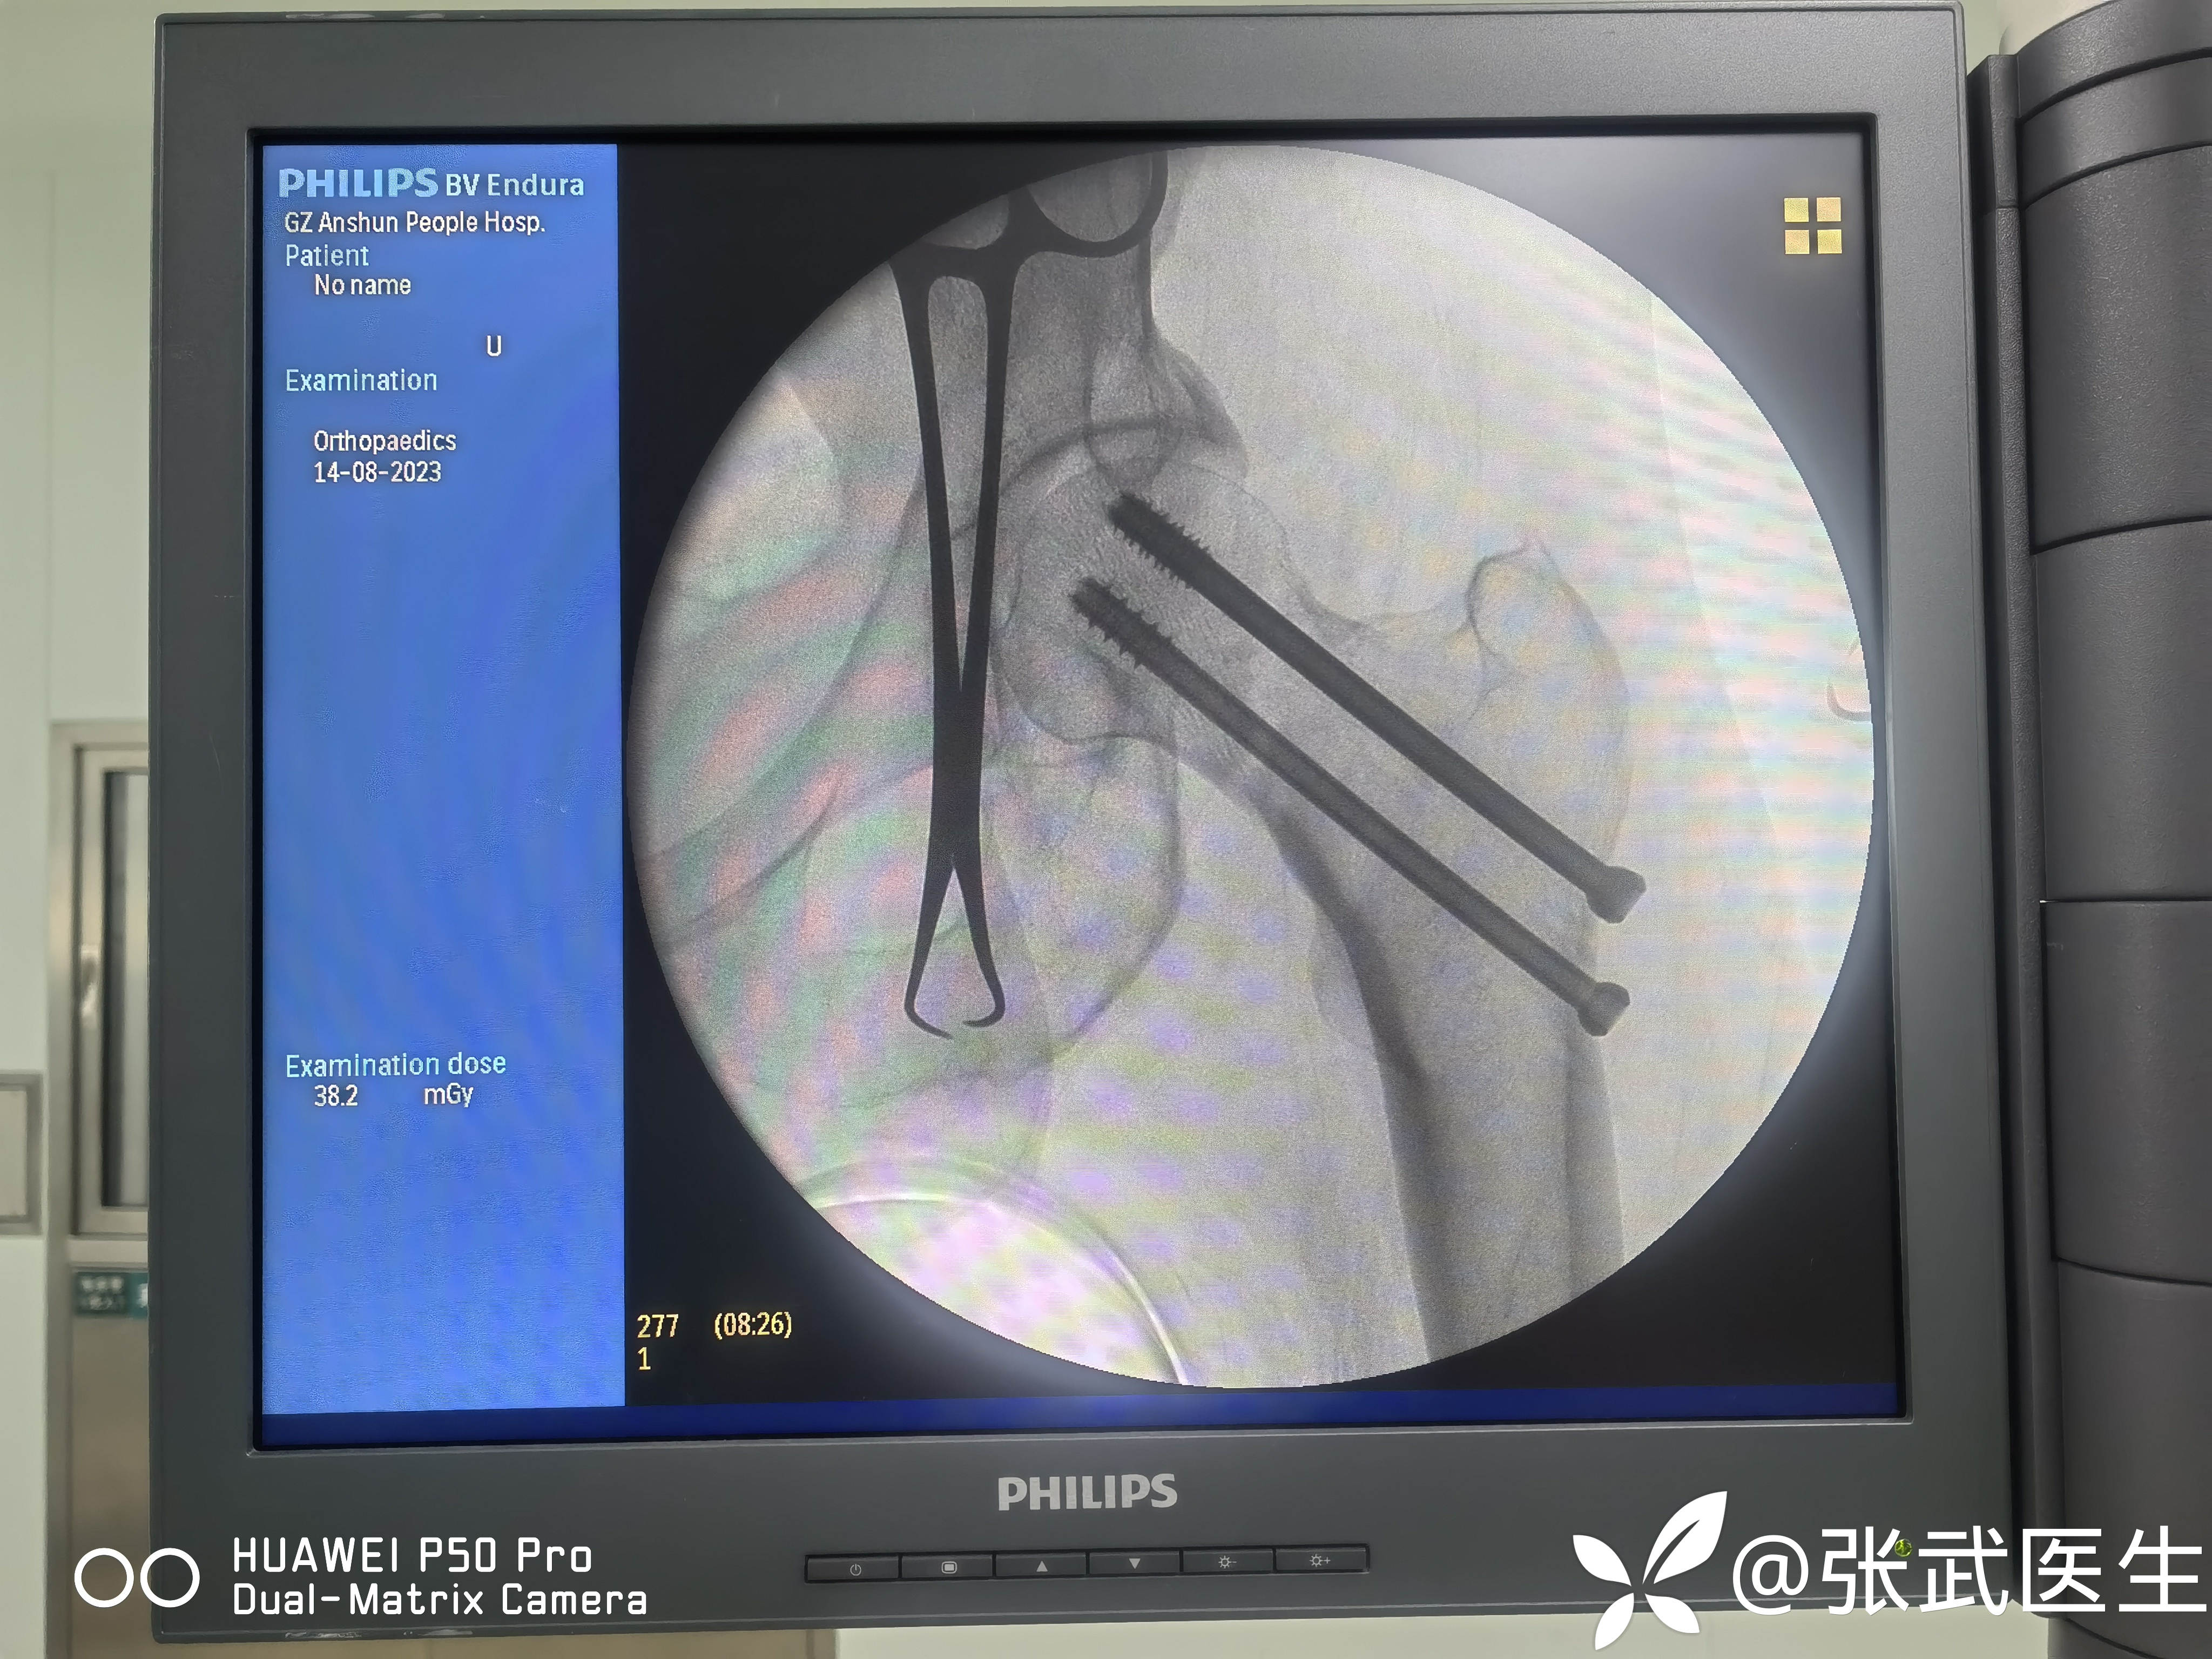

分别置入7.3mm*95mm 7.3mm*90mm 7.3mm*90mm三枚

置钉呈平行,分散,靠边。

手术顺利。